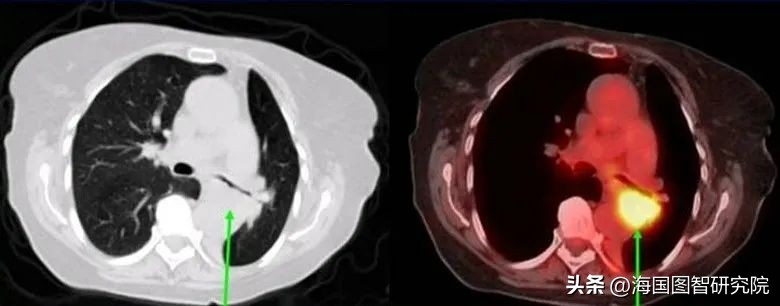

第一,利用核药可以检测出不易发现的癌症病灶,并监测治疗进度。目前较流行的两种新检测手段是PET-CT和SPECT。PET-CT指结合了PET和CT优势的联合诊断技术。PET即正电子发射断层扫描,使用放射性示踪剂的放射性物质使代谢过程和生理活动可视化,以评估癌细胞的进展和严重程度。其中,放射性示踪剂是由核同位素制成的诊断型核药,一般每种核同位素对应检测一种或某几种癌症。核药被注射入人体内后,会被细胞中的葡萄糖转运蛋白分子吸收,繁殖迅速的癌细胞会吸收更多的核药,在影像中呈现出异常的颜色。目前,PET-CT可以检测包括脑癌、子宫颈癌、肺癌和结直肠癌在内的多种癌症,还可以处理CT检测中的疑难病例,给出更精确的诊断。此外,《核医学杂志》的一项研究显示,在癌症分期准确性上,PET-CT的准确率(84%)明显高于单独使用CT(63%)或PET(64%)。核药对癌症诊断的另一贡献是SPECT技术,即单光子发射计算机断层扫描。其原理与PET-CT相似,同样利用核药现实医学影像,可用于检测骨癌或监测癌症治疗进展。例如,通过使用含碘-123或碘-131的核药对甲状腺癌患者进行检测,可在治疗前期精确癌症分期,在治疗后识别新转移或治疗失败迹象,以及在治疗结束后的长期随访中评估转移风险。简言之,核药与PET-CT或SPECT技术联合,可以提高癌症诊断的精确度,在治疗前后监测治疗效果。

图2:CT与PET图像对比

来源:美国国立卫生研究院

https://www.nibib.nih.gov/science-education/science-topics/nuclear-medicine